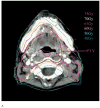

Methods and materials: Between 1996 and 2005, all patients with head-and-neck cancer treated with parotid gland-sparing IMRT in prospective studies underwent a dental examination and prophylactic treatment according to a uniform policy that included extractions of high-risk, periodontally involved, and nonrestorable teeth in parts of the mandible expected to receive high radiation doses, fluoride supplements, and the placement of guards aiming to reduce electron backscatter off metal teeth restorations. The IMRT plans included dose constraints for the maximal mandibular doses and reduced mean parotid gland and noninvolved oral cavity doses. A retrospective analysis of Grade 2 or worse (clinical) ORN was performed.

Results: A total of 176 patients had a minimal follow-up of 6 months. Of these, 31 (17%) had undergone teeth extractions before RT and 13 (7%) after RT. Of the 176 patients, 75% and 50% had received >or=65 Gy and >or=70 Gy to >or=1% of the mandibular volume, respectively. Falloff across the mandible characterized the dose distributions: the average gradient (in the axial plane containing the maximal mandibular dose) was 11 Gy (range, 1-27 Gy; median, 8 Gy). At a median follow-up of 34 months, no cases of ORN had developed (95% confidence interval, 0-2%).